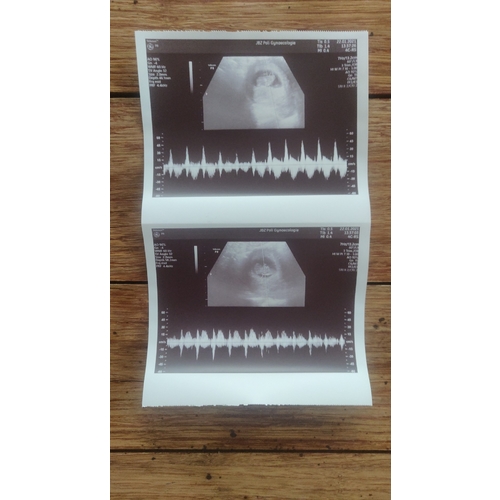

Update vandaag precies 10.0 wkn zwanger en 2 hele mooie hartjes mogen horen. 馃グ